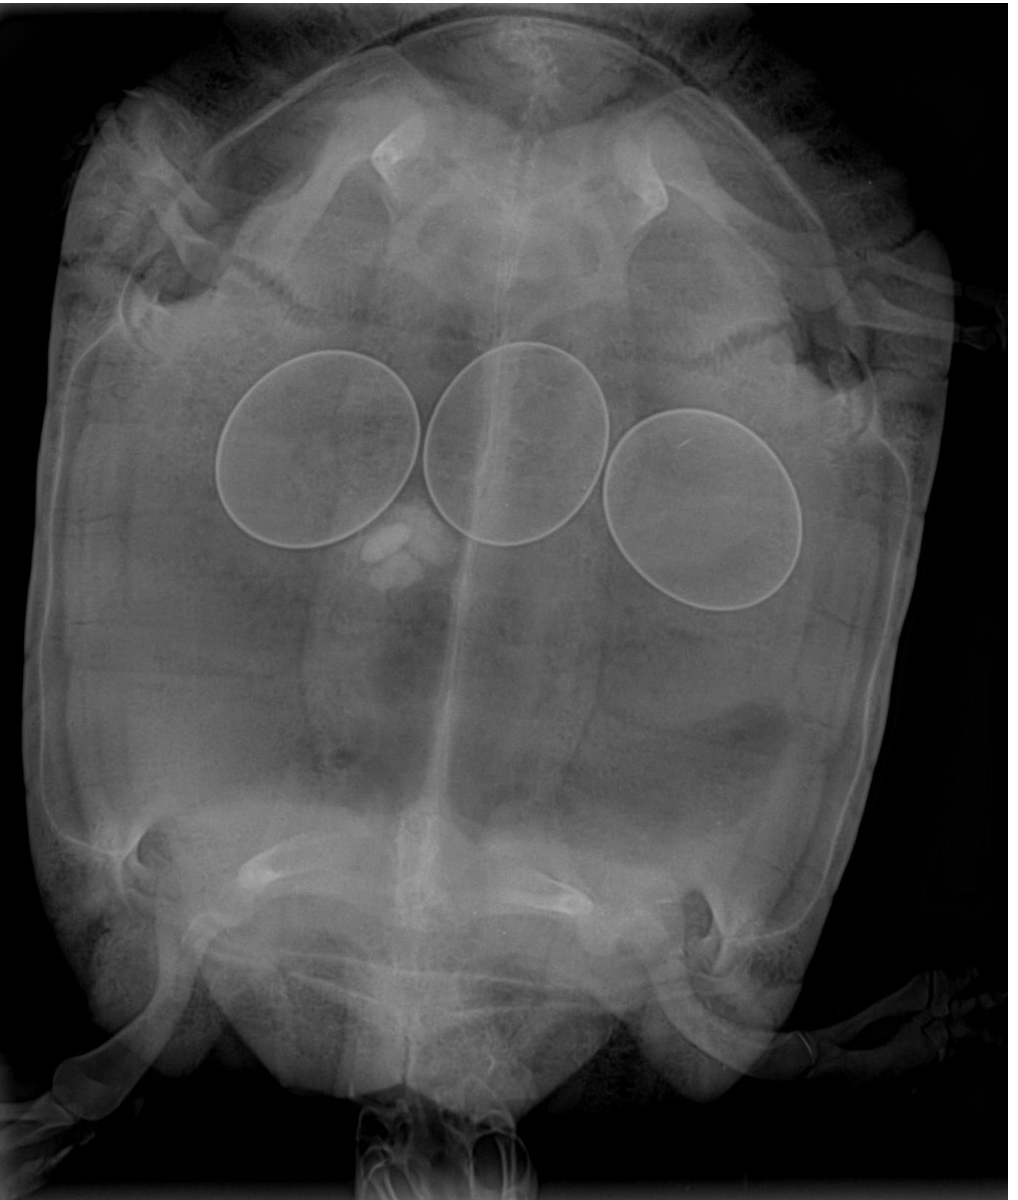

Diagnostic Imaging: Radiography is the gold standard for visualizing retained eggs. Ultrasound can also be useful in certain cases.

Photo credit: Uwe Gille (Creative Commons)